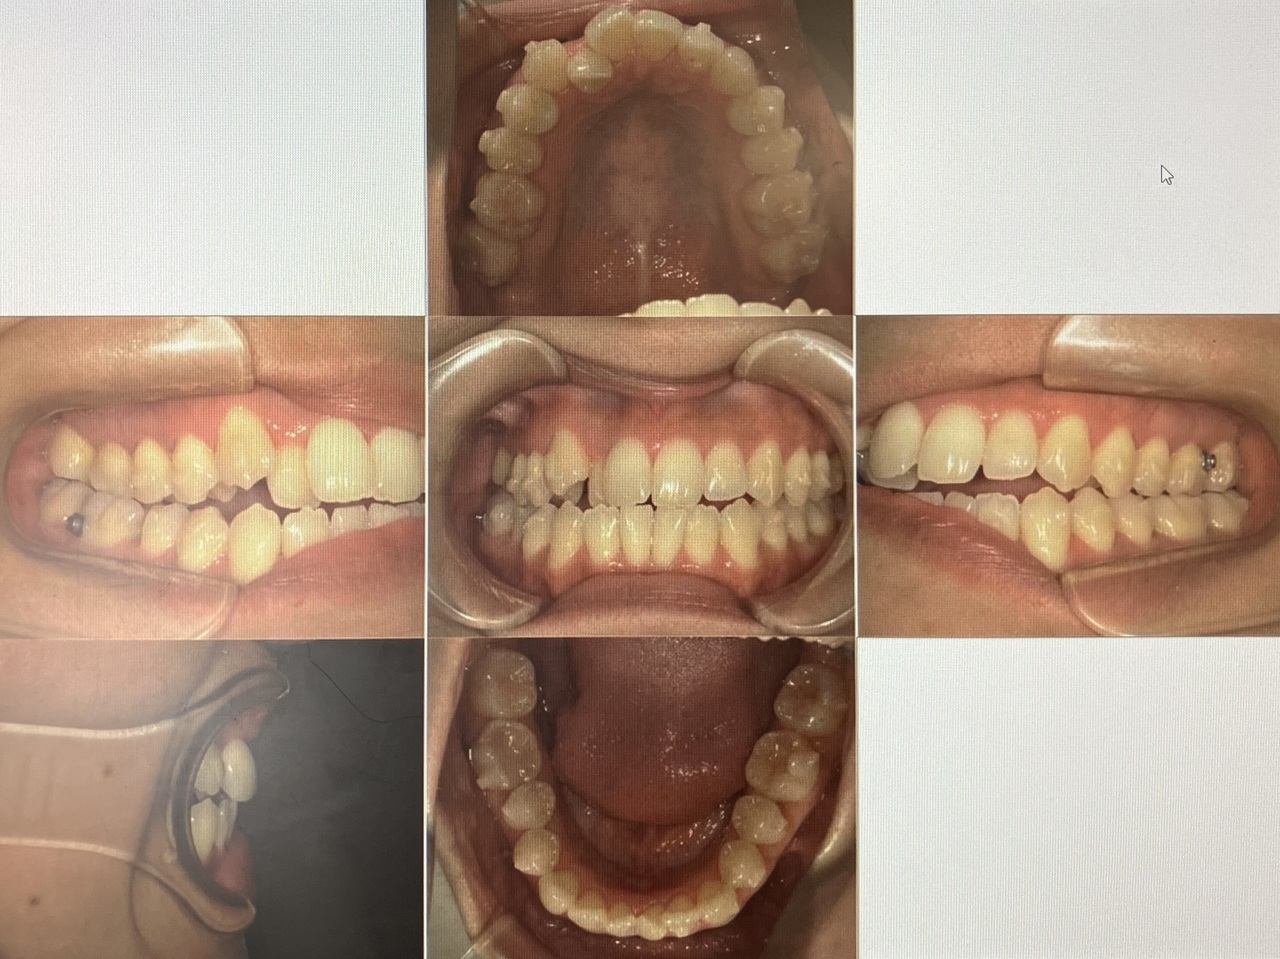

スタッフのインビザラインの経過です!

今、10枚目のアライナーになりました。

奥歯の隙間が開いてきて歯が動いているのが実感できています。